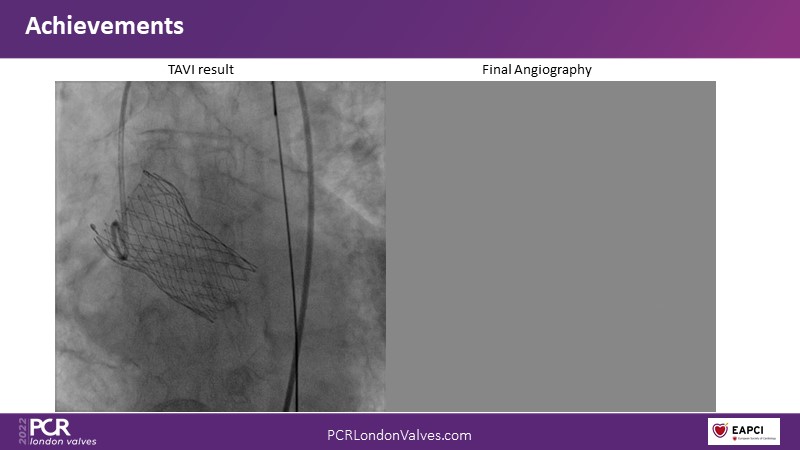

Transfemoral TAVI access using intravascular lithotripsy in patients with challenging peripheral vascular disease

Watch this session to appreciate why it is better to tackle difficult transfemoral access rather than considering alternative access strategies and understand how intravascular lithotripsy mitigates procedural risk.